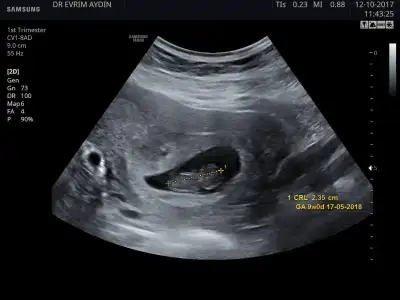

mrb biz de bugün doktora gittik doktor amca cinsiyetimizi ihtimal dahilinde söyledi siz de bir cinsiyet tahmininde bulunur musunuz çok merak ediyorum bu arada ikili testimi de yaptırdım 55 lira verdim bu ayın sonunda sonucunu alacagim